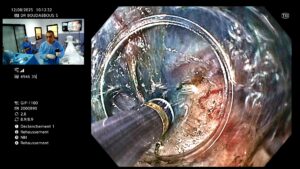

🔍 Déroulement de la procédure

- Réalisée sous anesthésie générale.

- Un endoscope flexible est introduit par la bouche.

- Le médecin crée un tunnel sous la muqueuse œsophagienne.

- Il sectionne les fibres musculaires du SIO responsables de l’obstruction.

- Le tunnel est refermé avec des clips endoscopiques.